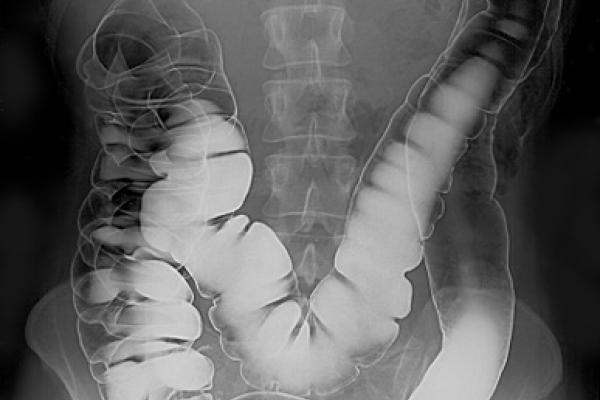

عکسبرداری با اشعه ایکس از روده بزرگ

در این روش، با استفاده از یک ماده ای به نام باریوم می توان پولیپ ها، تومورها و تغییرات بافت داخل روده بزرگ و مقعد را دید.

همانند کولونوسکوپی مجازی، هر گونه ناهنجاری که با این روش دیده می شود نیاز به پیگیری با کولونوسکوپی واقعی دارد.